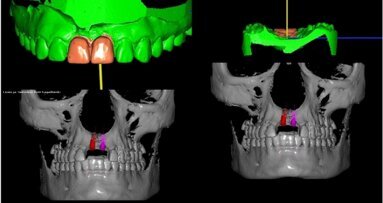

_9. Finał. Po tak przygotowanym planowaniu, a w praktyce pewności, że jesteśmy w stanie dać pacjentowi to, czego oczekuje i na co się z nim umówiliśmy, przystępujemy do ostatecznego wykonania leczenia. Implantolog wkręca implanty na podstawie wcześniej wydrukowanego w systemie wydruku 3D klucza implantologicznego i jeśli to możliwe, od razu obciąża je tymczasowymi koronami przygotowanymi z PMMA. Ta procedura sprawdza się szczególnie przy implantacji natychmiastowej. Poza tym, że jest opatrunkiem, pozwala pięknie zachować brodawkę dziąsłową. Wszyscy implantolodzy doskonale zdają sobie sprawę z tego, jak bardzo trudne jest ponowne „wybudowanie” brodawki dziąsłowej, jeśli ją utracimy. Przy implantacji natychmiastowej i tymczasowej koronie wykonanej w technologii CAD/CAM, dostosowanej w gabinecie, minimalizujemy ryzyko powikłań z tym związanych.

Żeby sprostać wymaganiom pacjentów i skrócić do minimum czas oczekiwania na pracę finalną, rozpoczęliśmy ostatnio współpracę z firmą Zimmer, która w swojej ofercie wprowadziła kilka lat temu implanty z metalu trabekularnego. Dlaczego ten rodzaj implantów? Trabecular Metal Implant to pierwszy na świecie implant wykonany z biokompatybilnego i pasywnego pierwiastka Ta (tantal). Technologię stosowaną od przeszło dekady w implantach ortopedycznych firma Zimmer wykorzystała do produkcji implantów stomatologicznych. Powstał w ten sposób materiał trójwymiarowy o strukturze kości gąbczastej. Umożliwia on formującej się tkance kostnej nie tylko obrastanie implantu od zewnątrz, ale również wrastanie w jego strukturę, co zwiększa stabilizację. Firma podaje, że dzięki zastosowaniu implantów Trabecular Metal możliwe jest zakończenie leczenia w czasie 2 tygodni od implantacji.

W praktyce implantolog, nie widząc zupełnie pacjenta, mając wgląd w wykonane wcześniej procedury, mógłby na umówiony dzień zabiegowy przyjechać z gotowym szablonem chirurgicznym, świetnie dobranymi implantami i wyfrezowanymi koronami tymczasowymi. Oczywiście, to przypadek dość jednostkowy, bo lekarz lubi skonsultować wcześniej pacjenta i przede wszystkim zdobyć jego zaufanie, ale to, że jest to w ogóle możliwe, to właśnie efekt DIGITALIZACJI!

Konfiguracja programu umożliwia precyzyjne umieszczenie implantu w kości z zachowaniem proporcji pod przyszła pracę protetyczną (kąt wychylenia oraz odległości pomiędzy punktami). Wykorzystane w nim rozwiązania pozwalają na przeprowadzenie przyszłego zabiegu implantacji w taki sposób, jaki zaplanowany został wirtualnie (za pomocą szablonu, który tworzymy). Szablon drukujemy na drukarce 3D lub frezujemy w CNC i tym sposobem uzyskujemy swoisty pozycjoner, który wskaże dokładne położenie implantu zarówno dla uzyskania dobrego efektu kosmetycznego, jak i dla głębokości jego wprowadzenia. Błąd ludzki ograniczamy do minimum. Dla systemów implantologicznych, które w swojej ofercie proponują tuleje prowadzące, szablon implantologiczny wykonywany jest odpowiednio z miejscem na tuleję.